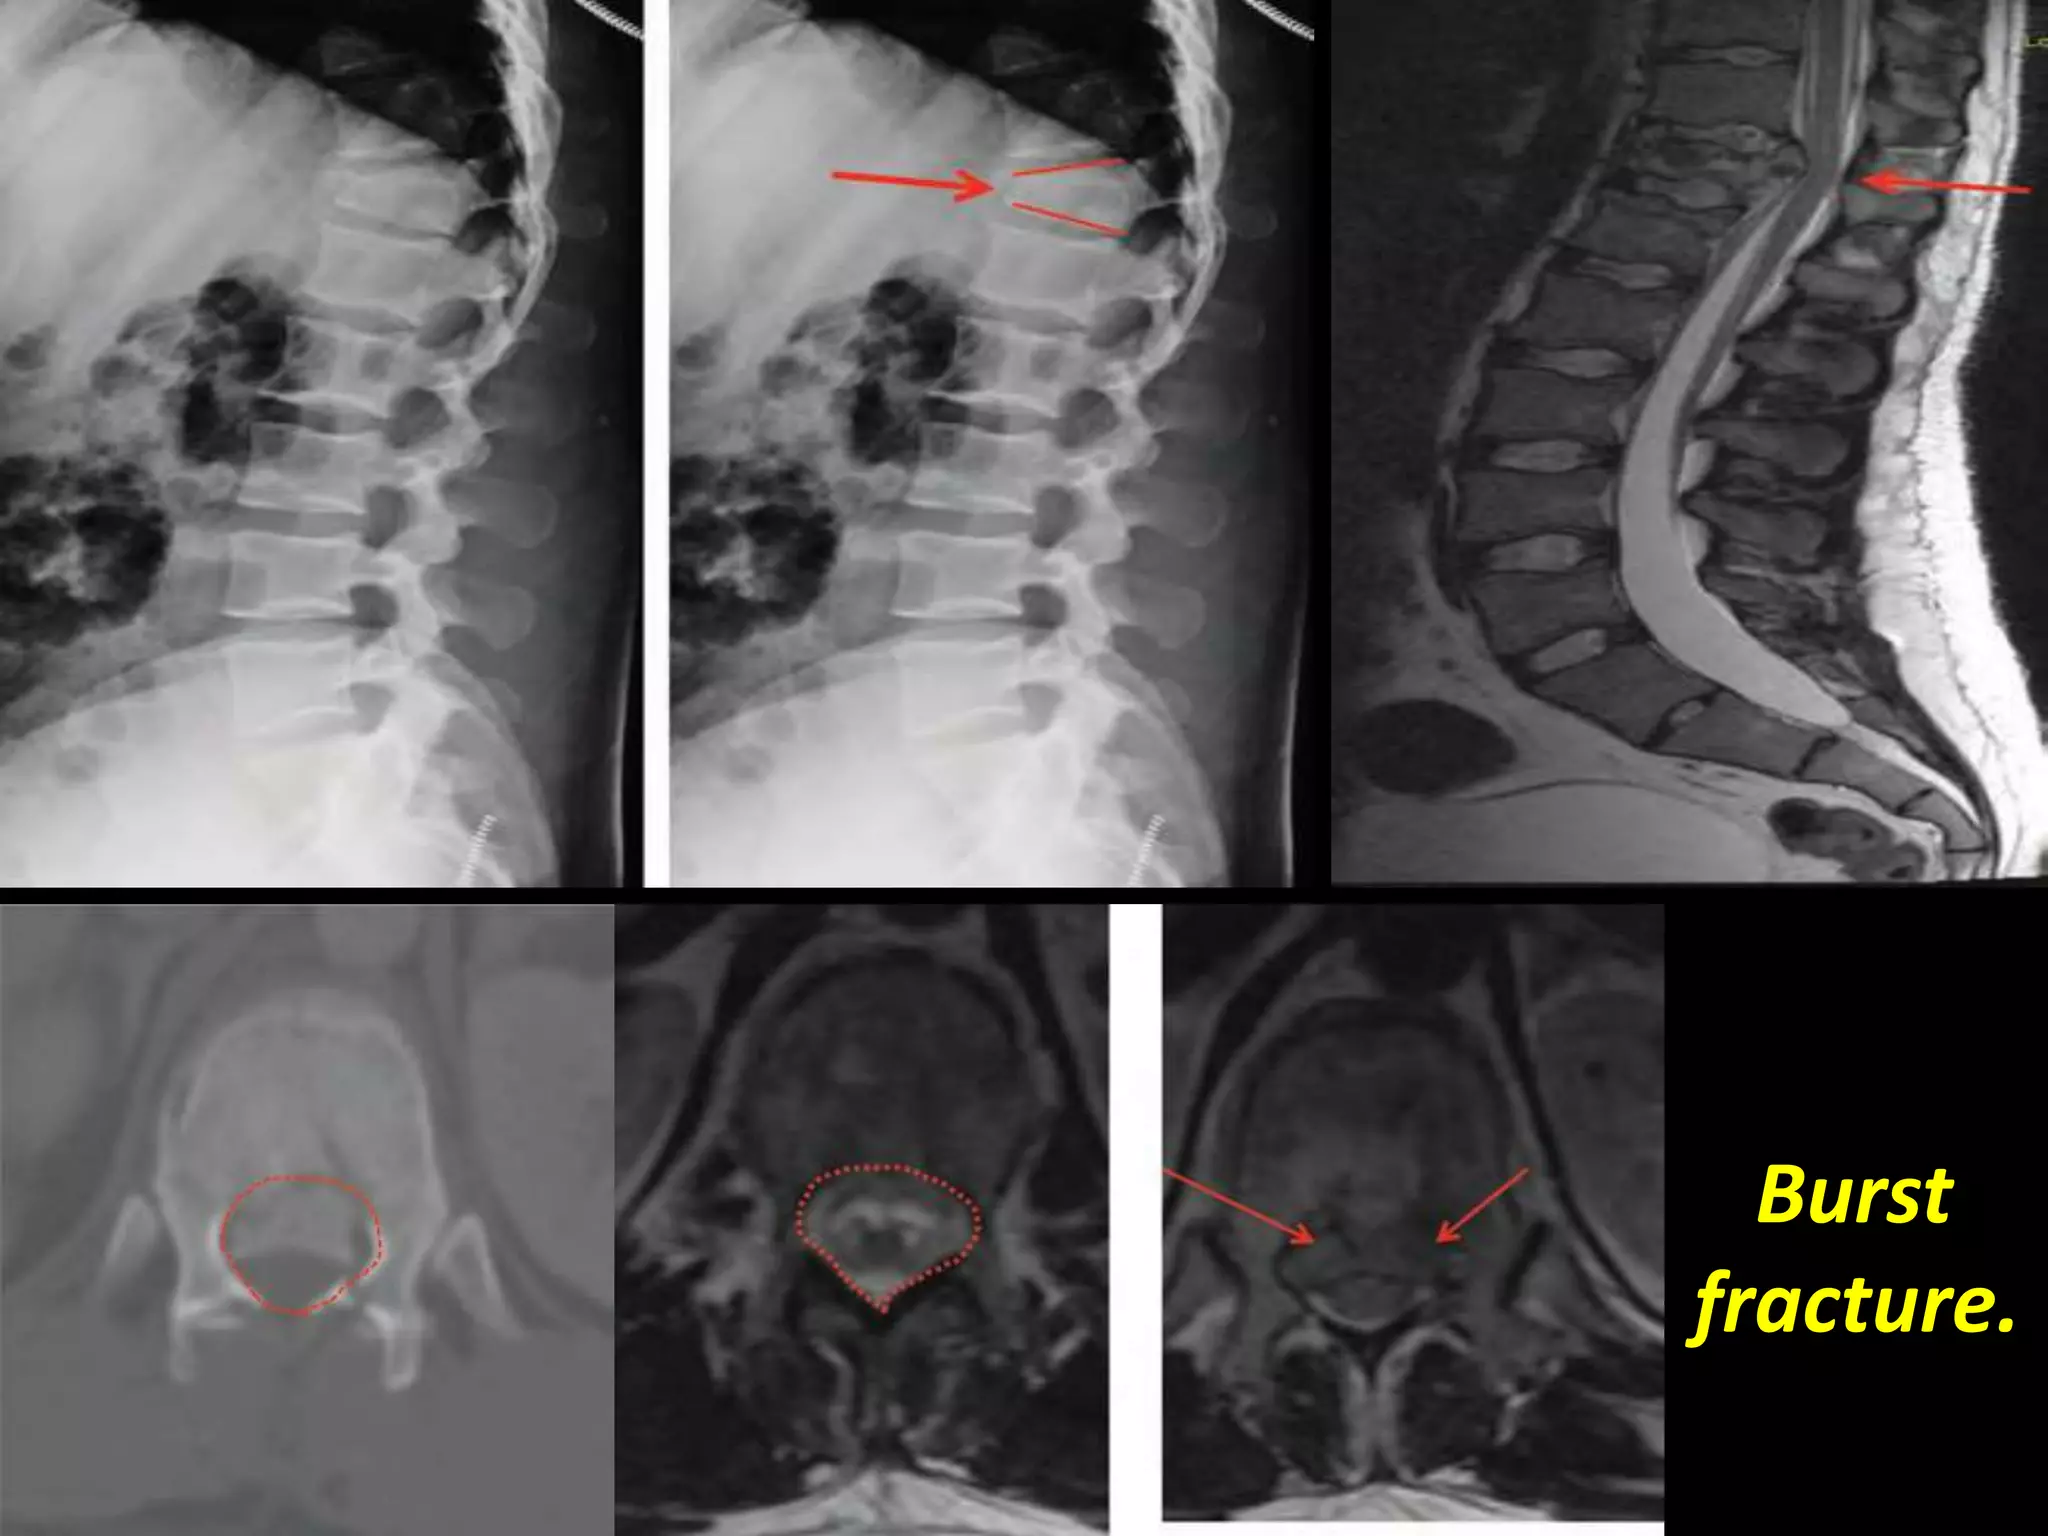

Coronal T2W image dorso lumbar spine of a 29 yr old male

patient showing burst fracture(arrow) of L3 vertebra.

Burst fracture.

Burst

fracture.

Burst vs. Anterior Wedge Fx:

• Anterior wedge - anterior column – stable.

• Burst - 2-3 columns – unstable.

• Important to differentiate.

– Look for posterior vertebral concavity.

– CT for evaluation of posterior vertebral body,

fracture of posterior elements.

– As many as 20% of burst fractures may be

missed if radiographs alone are used.

– MRI for ligamentous disruption / neuro sx.

Sagittal T2W

image of 23yr

old male

showing burst

fracture with

anterior

wedging(arrow)

of L1 vertebra.